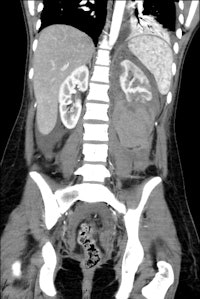

An 18-year-old female with "after-party amnesia" presented with severe stomach pain and bruises to the head. An investigation showed vaginal bleeding was from the bladder. Full-scale emergency room investigation showed severe left kidney fracture and contusion, but intact vessels and ureter. Three-month follow-up renography shows 28% kidney function on left side as the only sequelae. Image courtesy of Dr. Vibeke Logager.